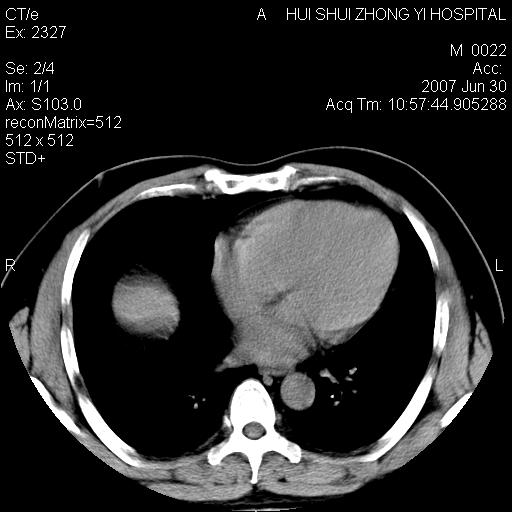

肝右叶密度减低区?

支持双肾结石,肝右叶低密度影为胆囊部分容积效应。

肝右叶低密度影为胆囊部分容积效应?为什么s43.0层面下来不见胆囊影,而是相隔了一层才见胆囊影。这是按我们扫描的顺序发的,但是是追加扫描的。

肝右叶低密度灶,增强!

支持双肾结石,肝右叶低密度影为胆囊部分容积效应

病人呼吸动了,第四层应该在第五\\六层之间。肝右叶低密度影为胆囊部分容积效应。双肾结石。

考虑:1、水平肝;